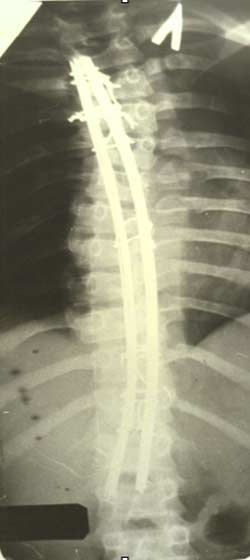

История создания устройства для

оперативного лечения сколиотической

деформации началась в 70-е годы. А.А.

Гайдуков и Л.Л. Роднянский предложили

динамическую конструкцию эндокорректора.

Она представляла собой пластины уложенные

вдоль позвоночника на вершине деформации

и фиксированные проволокой к дужкам

или остистым отросткам позвонков на

нескольких уровнях. Но данная конструкция

не оправдала надежд авторов и была

оставлена.

|

В дальнейшем

А.А. Гайдуков разработал и создал

эндокорректор с деротационными скобами

с фиксацией в блоках креплений на

нескольких уровнях. Данный эндокорректор

позволил эффективно на 60-100% корригировать

деформацию при сколиозе III-IV степени.

Но тяжелая многочасовая операция,

травматичность вмешательства, проволочная

фиксация и нередкие неврологические

осложнения ограничивали применение

данной методики.

Л.Л.

Роднянский предложил для коррекции

сколиотической деформации одно-пластинчатый

эндокорректор. Методику характеризовала

малая травматичность и безопасность

оперативного вмешательства. Однако,

недостаточная жесткость конструкции,

малое число блоков крепления корректора

не позволяли оперировать тяжелые формы

деформации. В случаях вмешательства у

пациентов с начальной стадией заболевания,

с деформацией I-II степени не удавалось

избежать прогрессирования искривления.

В послеоперационном периоде происходила

достаточно быстрая потеря коррекции и

в общем она составляла приблизительно

40%. Кроме этого достоверно нарастала

ротационная деформация позвоночника

на вершине искривления.